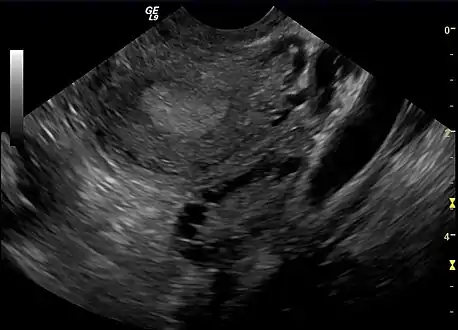

The syndrome acquired its most widely used name due to the common sign on ultrasound examination of multiple (poly) ovarian cysts. These "cysts" are in fact immature ovarian follicles. The follicles have developed from primordial follicles, but this development has stopped ("arrested") at an early stage, due to the disturbed ovarian function. The follicles may be oriented along the ovarian periphery, appearing as a 'string of pearls' on ultrasound examination.[79]

Polycystic ovary as seen on sonography

- Gynecologic ultrasonography, specifically looking for small ovarian follicles. These are believed to be the result of disturbed ovarian function with failed ovulation, reflected by the infrequent or absent menstruation that is typical of the condition. In a normal menstrual cycle, one egg is released from a dominant follicle – in essence, a cyst that bursts to release the egg. After ovulation, the follicle remnant is transformed into a progesterone-producing corpus luteum, which shrinks and disappears after approximately 12–14 days. In PCOS, there is a so-called "follicular arrest"; i.e., several follicles develop to a size of 5–7 mm, but not further. No single follicle reaches the preovulatory size (16 mm or more). According to the Rotterdam criteria, which are widely used for diagnosis of PCOS,[10] 12 or more small follicles should be seen in a suspect ovary on ultrasound examination.[21] More recent research suggests that there should be at least 25 follicles in an ovary to designate it as having polycystic ovarian morphology (PCOM) in women aged 18–35 years.[88] The follicles may be oriented in the periphery, giving the appearance of a 'string of pearls'.[89] If a high-resolution transvaginal ultrasonography machine is not available, an ovarian volume of at least 10 ml is regarded as an acceptable definition of having polycystic ovarian morphology. rather than follicle count.[88]